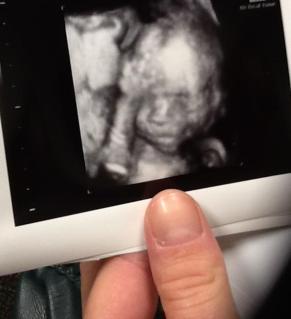

Little more than a week ago, The Man and I went for our ultrasound. The big one. And you’ll never believe it, but we will be welcoming another sweet little princess to our home. I cannot tell you how thrilled we are. I guess God thinks that we are starting to get the hang of it by now. The Man is positively glowing and I am beside-myself-giddy.

But we also found out something else, a fairly serious complication that I wasn’t expecting. It’s something called a complete previa. The doctor said it would probably cause problems later on in the pregnancy and I would have to deliver by c-section. New territory, but I figured we’d cross that bridge when we got there. A few short days later, I was admitted to the hospital for problems already. I was reluctantly released from the hospital under strict doctor’s orders. (And when I arrived home, The Man had a lovely fresh cup of chocolate coffee waiting for me. How is that for love?)